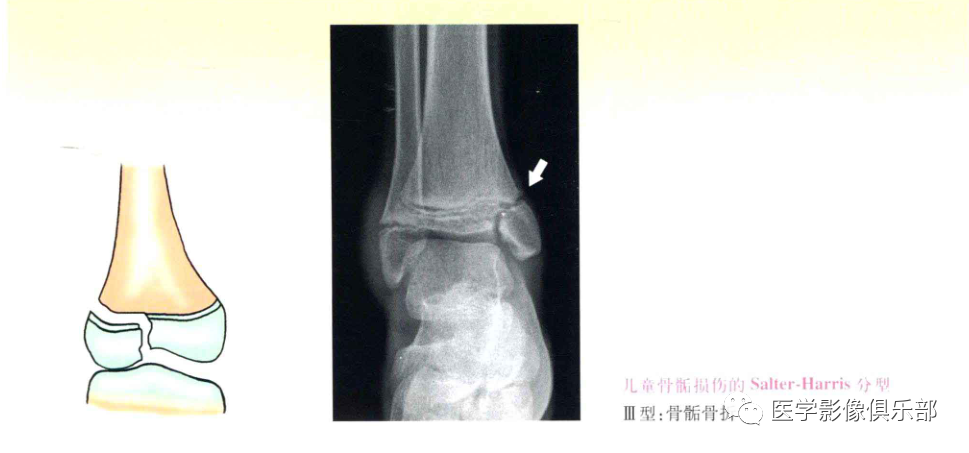

Ⅲ型:骨骺骨折;

Ⅰ、Ⅱ型损伤,骨折线不经过骨骺,通常不造成生长发育障碍,Ⅲ、Ⅳ型累及骨骺,可造成生长阻滞和进行性畸形。